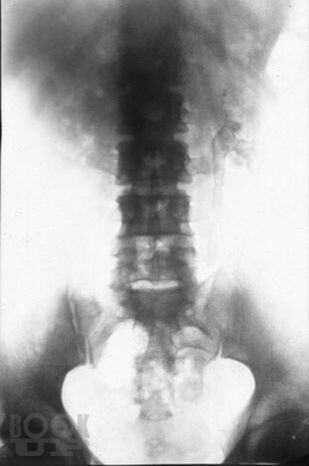

Туберкулез мочеполовой системы

Кратко изложены вопросы этиологии, патогенеза, классификации, диагностики илечения туберкулеза мочеполовой системы. Пособие подготовлено с учетом требований ФГОС ВПО (приказ Минобрнауки РФ от 31.05.2011 г. № 1975), соответствует типовой образовательной программе по специальности 060101 «Лечебное дело», предназначено для студентов 4–5 курсов лечебного факультета и направлено на формирование профессиональных компетенций вих будущей лечебно-диагностической, реабилитационной и профилактической деятельности (ПК 10, 14, 20, 26, 35).